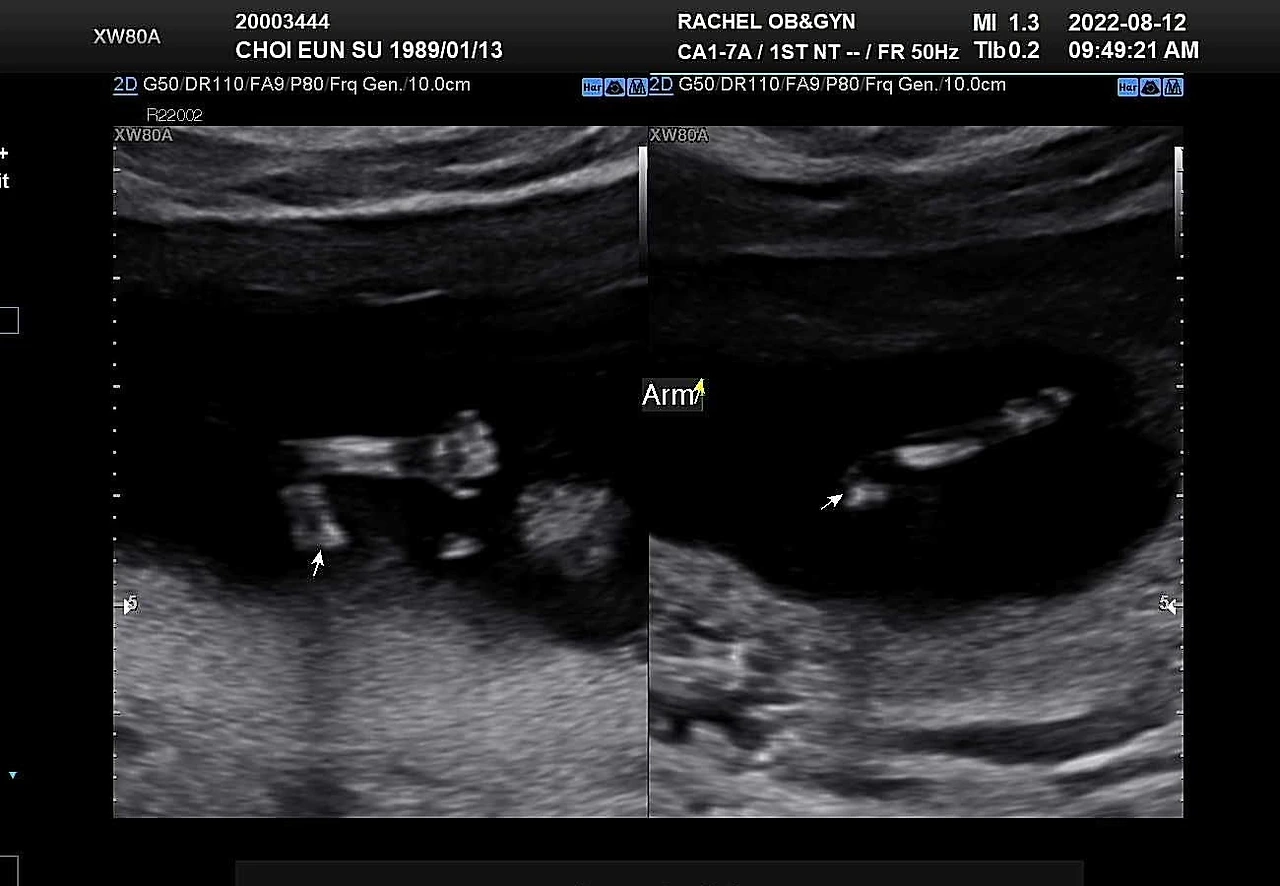

13주 1일. 1차 기형아 검사 결과를 들으러 병원에 갔다. 이제는 꽤 자란 모습이 눈에 보여서 심박수는 따로 재지 않고 열심히 뛰는 심장만 보여주셨다. 초음파를 대자마자 발도 구르고 손도 휘젓는 아기. 일주일 사이에 금세 자라 손가락 발가락도 더 잘 보이고, 코부터 턱까지 얼굴 옆 라인도 꽤 사람답게 보여서 기특했다.

*13주차 초음파 사진